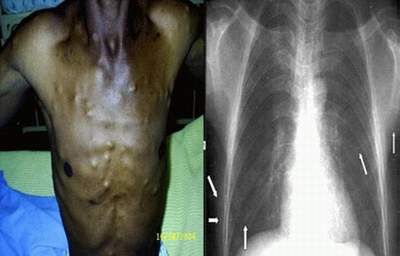

Tổn thương trên “người gạo” do nhiễm sán lợn.

Tùy vị trí của nang ấu trùng sán mà có các tổn thương: ở da thường gặp các nang  nhỏ bằng hạt đỗ hoặc hạt dẻ, tròn, chắc, không đau, di động trên nền sâu và lăn dưới da, màu da ở trên bình thường. U nang sán thường nổi ở mặt trong cánh tay hoặc ở bất kỳ vị trí nào và có tính chất đối xứng. Rất hiếm khi các u nằm bên cạnh dây thần kinh và gây đau dây thần kinh. U nang sán sau nhiều năm sẽ bị vôi hoá, lúc này có thể phát hiện được bằng chụp Xquang.

Xét nghiệm chọc hút tại nang ấu trùng có một ít dịch trong. Xét nghiệm phân có thể thấy đốt sán và trứng sán. Sinh thiết u nang ở da tìm thấy ấu trùng sán lợn. Chụp Xquang não thất hoặc soi đáy mắt phát hiện thấy u nang sán hoặc ấu trùng sán lợn.